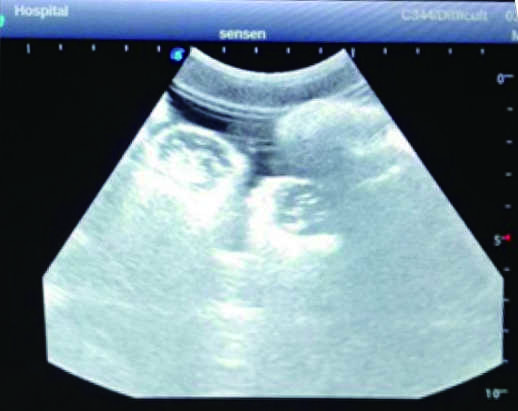

2) Real clinical ultrasound images with clear anatomical structures like intestines, part of the liver, arteries and veins, etc.